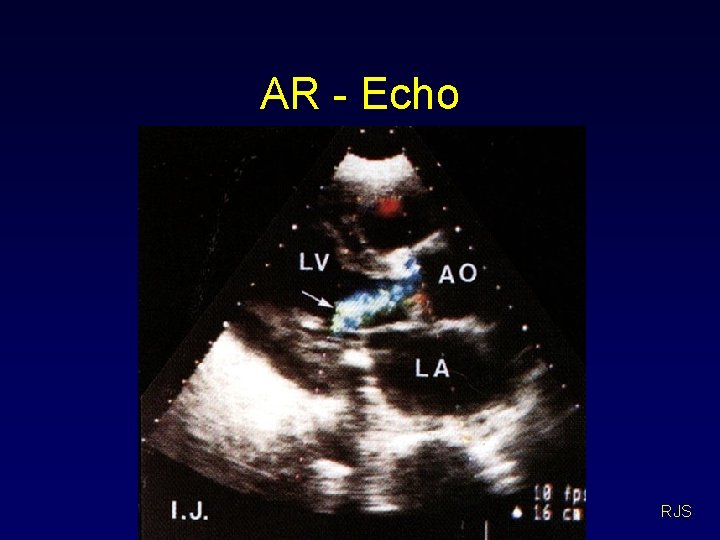

AR investigations • • ECG – LVH X-ray – abnormal aorta, large heart Echo – AR, LV dilation, dissection Angiogram – AR, LV dilation RJS

AR - Echo RJS